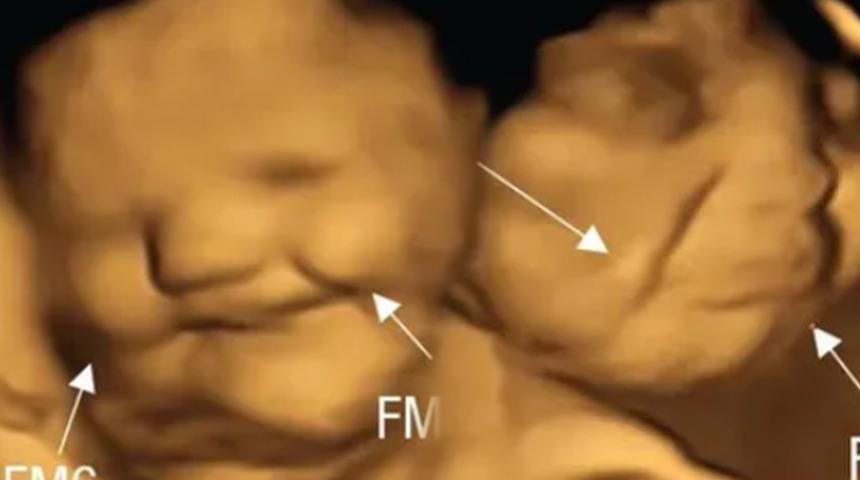

Independent'ın haberine göre, Durham Üniversitesi'nden bilim insanları, fetüslerin farklı tatlara tepki verip vermediğini görmek için 4D ultrason taramaları kullandı. Durham Üniversitesi Psikoloji Bölümü'den Beyza Üstün'ün liderliğindeki araştırma ekibi, fetüslerin belirli tatları ayırt edip edemediğini görmek için 18-40 yaşları arasındaki 70 hamileyi iki gruba ayırıp ultrason görüntülerini inceledi. Psychological Journal'da yayımlanan çalışmada araştırmacılar, annenin diyetinden gelen tat ve koku bileşimli aromaların 32 ila 36'ncı gebelik haftalarında amniyotik sıvıda hissedildiğini tespit etti.

Ultrason taramasından 20 dakika önce bir gruptan toz karalahana, diğer gruptan toz havuç tüketmeleri istendi.Çalışmada, "Tek dozluk bir kapsülün maternal tüketimi yoluyla aktarılan tatlara karşı insan fetal duyarlılığının ilk doğrudan kanıtını, kare kare fetal yüz hareketlerini ölçerek rapor ediyoruz" denildi.

Çalışmaya katılan anne adaylarının raporlama öncesinde herhangi bir gıda tüketmemesi talep edildi. Çalışma kapsamında bir grup anne toz havuç tüketirken diğer grup ise lahana tozu yedi. Fetüslerin reaksiyonunu doğumdan önce gösteren ilk çalışma olarak nitelendirilirken makalede imzası olan Dr. Benoist Schaal da sonuçların bu kadar net olmasını şaşırtıcı olarak değerlendirdi.